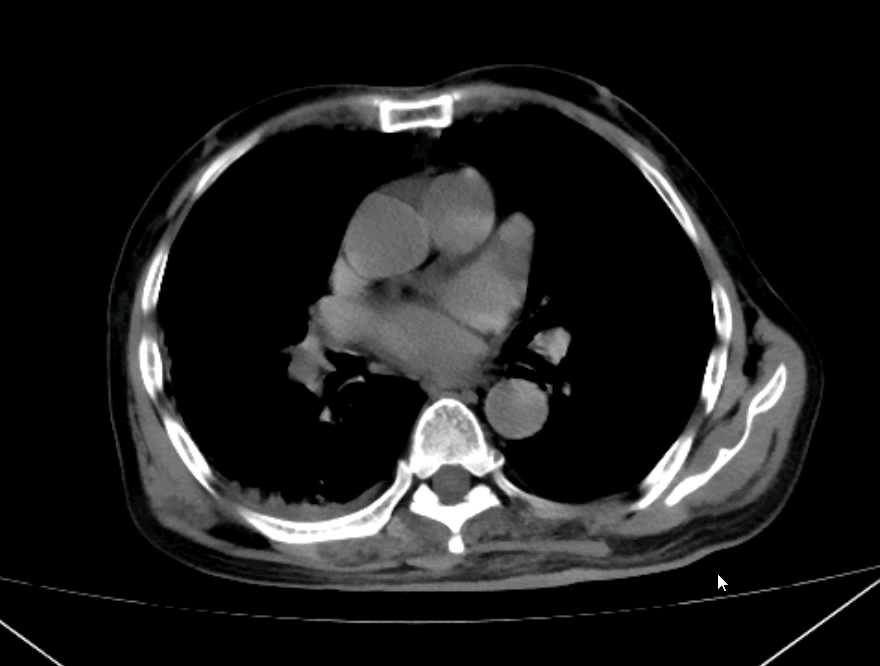

4、辅助检查:(2024-07-16)血常规示:白细胞计数:14.09x10^9/L↑;中性粒细胞绝对值:12.96x10^9/L↑;淋巴细胞绝对值:0.85x10^9/L↓;嗜酸性粒细胞绝对值:0.01x10^9/L↓;中性粒细胞百分比:92.00%↑;淋巴细胞百分比:6.00%↓;单核细胞百分比:1.90%↓;嗜酸性粒细胞百分比:0.10%↓;凝血功能示:纤维蛋白原降解:15.49ug/ml↑;D一二聚体:1.41ug/ml↑;心肌两项示:肌红蛋白:410.5ng/ml↑;N末端B型钠尿肽前体:3422pg/ml↑;呼吸道八联检查:甲型流感病毒:弱阳性+;电解质示:钠:130.7mmol/L↓;磷:0.55mmol/L↓;肝功能示:总胆红素:34.8umol/L↑;直接胆红素:14.7umol/L↑;间接胆红素:20.1umol/L↑;胆碱酯酶:4441U/L↓;肾功能示:尿素氮:8.54mmol/L↑;肌酐:171.9umol/L↑;血清胱抑素C:1.777mg/L↑;心肌酶四项示:肌酸激酶:352.3U/L↑;乳酸脱氢酶测定(速率法等):264.6U/L↑;α-羟丁酸脱氢酶:198U/L↑;心电图示:1、窦性心动过速;2、肢导联低电压;3、V6导联T波轻度改变。颅脑及双肺CT示:1、颅脑CT平扫未见异常,必要时请复查。2、左肺上叶下舌段及右肺中叶外侧段感染性病灶。3、心脏外形不大,主动脉壁及左侧冠状动脉走行区多发钙化斑。随机血糖:9.1mmol/L。

患者持续发热,激素,退热针,左氧氟沙星,派拉西林都无法退热,给予完善腹部ct及b超

目前来看bnp持续升高及肾脏,心肌酶,降钙素原持续升高,原因何在?请各位从影像上分析: